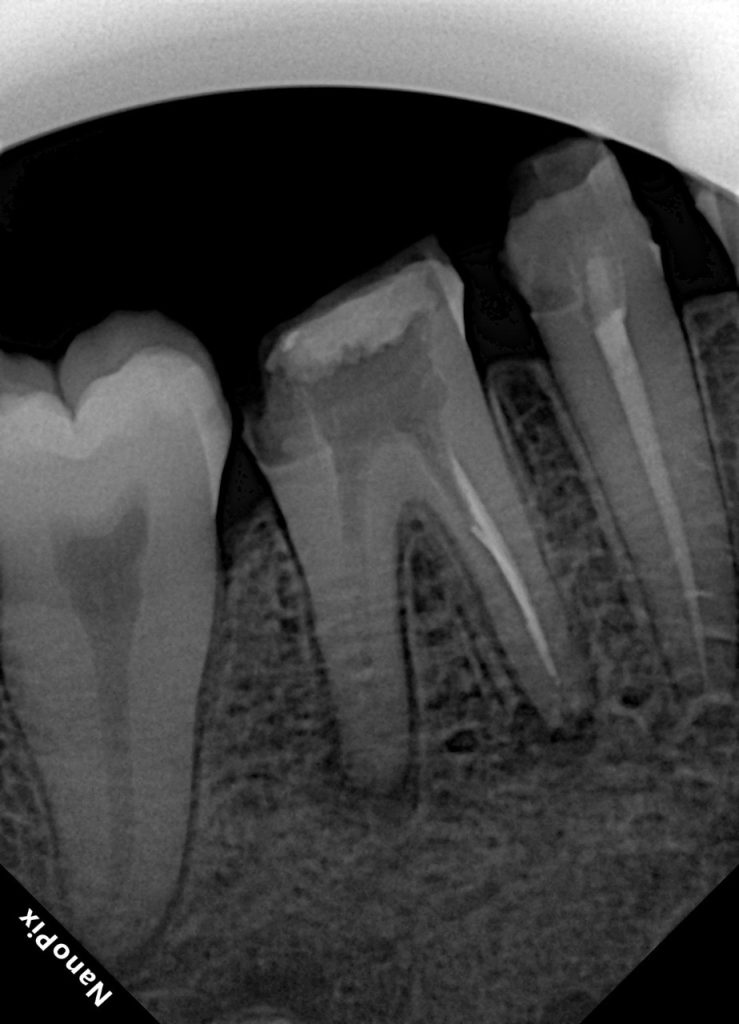

Patient presented with persistent dull pain in a previously treated mandibular molar (Fig 1). Radiograph revealed under-filled canals, apical radiolucency, and a fractured orifice opener lodged in the distal canal. Diagnosis: failed RCT with symptomatic periapical periodontitis.

- Fig 1: Pre-op radiograph showing broken file and defective obturation.